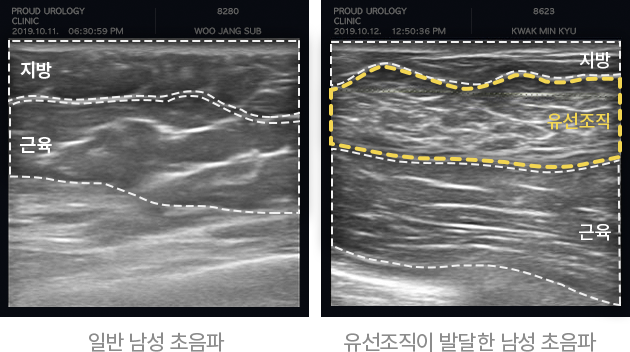

초음파를 통한 구분

하이스트는 고해상도 이미지를 구현하는 첨단 정밀 초음파

진단기(E-CUBE)를 통해

방사선 노출 없이 안전하게

유선조직 증식 여부를 정밀 검사합니다.

여유증의 유형

초음파 검사를 통해 유선조직 유무에 따라

지방형 여유증과 유선형 여유증으로 크게 나눌 수 있습니다.

(운동으로 개선 불가)